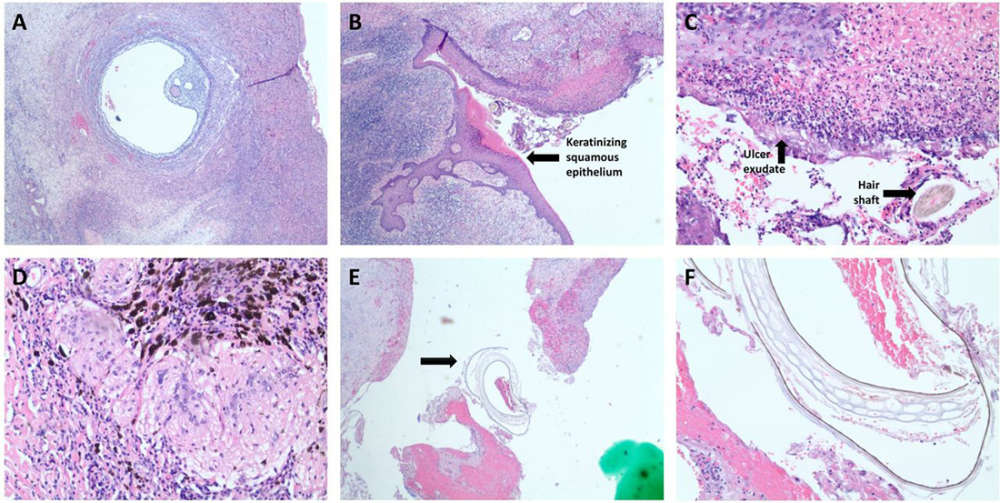

Az orvosi jegyzőkönyvek számtalan olyan feljegyzéseket tartalmaznak, amelyekben a bizonyos dolgok nem a legjobb helyen vannak, ám a BMJ Case Reports által közzétett legfrissebb dermoid cisztás eset übereli az összes eddigi esetet. Találtak már ugyanis emberi petefészekben szőrt, bőrt, fogszerű képződményeket meszesedés eredményeként, de ilyennel még sosem találkoztak az orvosok.

Először leválasztották a petefészket, amely mellett egy hatalmas ciszta volt. Az orvosok úgy írták le, hogy nagyon rossz szaga volt feltehetően egy szuperinfekció (kórokozóváltással járó felülfertőződés) eredményeként.

Aztán mikor feltárták a cisztát, zöldséget találtak benne. A tanulmány szerzői azt mondják, hogy az étel valószínűleg a nő belén lévő lyukon keresztül szivárgott ki, amely később „spontán zárult”, mivel a műtét során nem találtak semmiféle perforációt. Majd az anyag innen valahogy bekerült a petefészekbe.